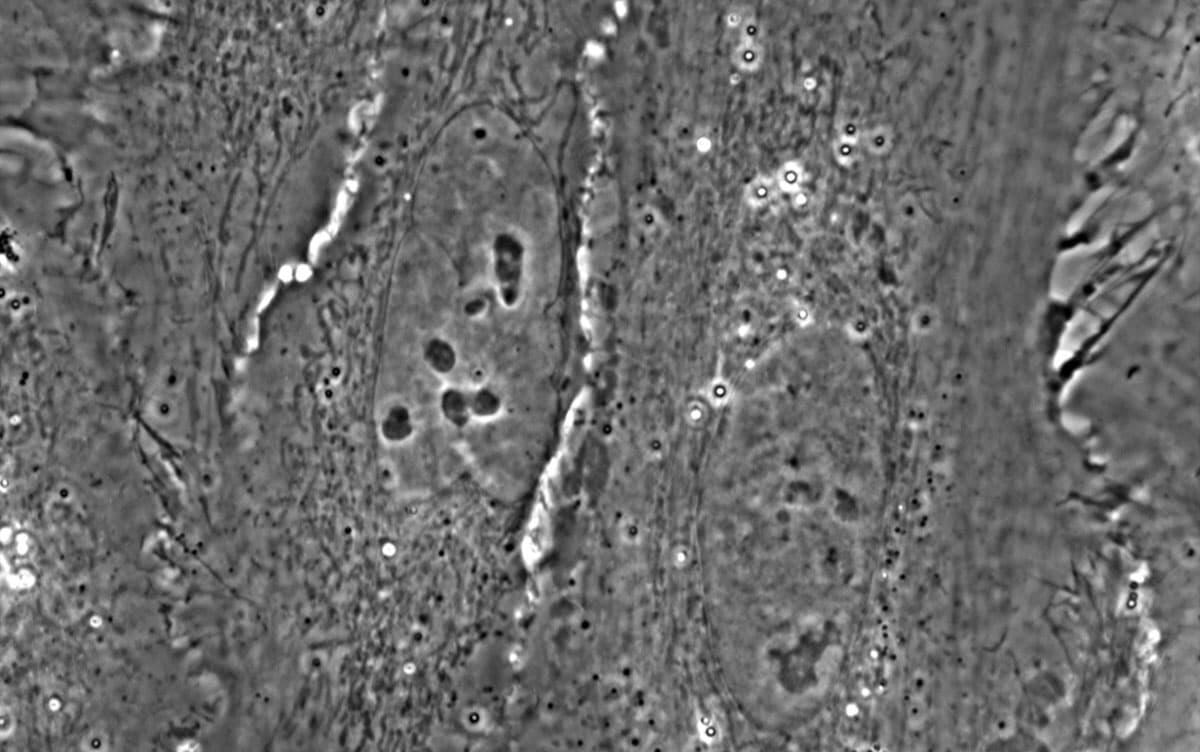

ハロ(光輪)と呼ばれる偽像の発生を抑制できる外部アポダイズド位相差顕微鏡を用い、核やミトコンドリアなどの細胞小器官を高精細に観察し、その動きや配置、形の制御が高い安定性をもつことを解明しました。また、構成成分が未解明の生体分子凝縮体様構造体を非標識で観察することにも成功しました。

本研究では、このハロを抑える光学的仕組みを導入した外部アポダイズド位相差(ExAPC)顕微鏡法を用い、細胞周期などの生命イベントにおいて、核や核小体、ミトコンドリアなど複数の細胞小器官を非標識のまま高精細に観察することに成功しました。さらに、構成成分が未解明の生体分子凝縮体様構造体を世界で初めて明瞭に可視化しました。加えて、脂肪滴の成長過程やミトコンドリアの分裂・融合、薬剤応答の観察を通して、個々の構造体が多様な動き(ヘテロジェナイティ)を示しながらも、全体としては高い秩序と安定性(ロバスト性)を維持していることを明らかにしました。